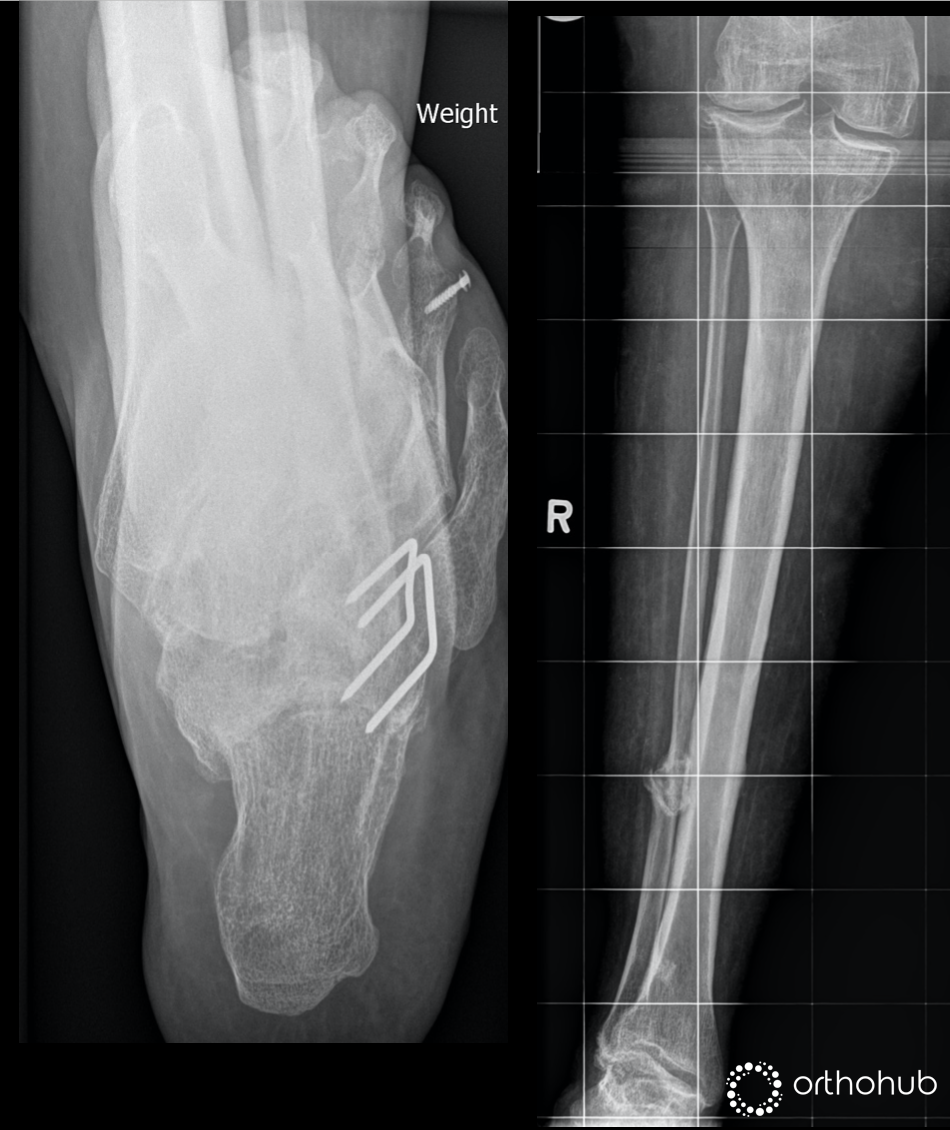

32 yrs female, previous PFFD. She had 10cm of lengthening and multiple previous surgeries

Major problems:

Lateral right knee pain

Lateral compartment OA, grade-4

Tricompartmental OA changes

Valgus mal-alignment

Right hip pain (she has OA hip on the same side)

Valgus deformity of the leg

Mild valgus of right tibia

Valgus right ankle with lateral OA changes (secondary to the longstanding valgus leg)

Stiff hindfoot and midfoot